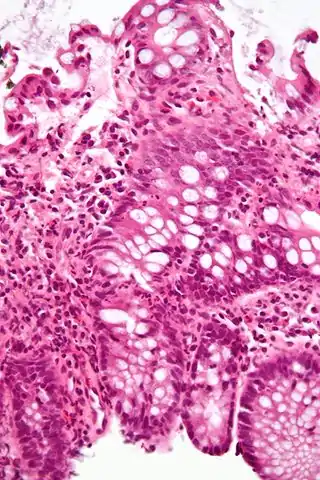

Una investigación importante en la evaluación de la colitis es la biopsia. Se extrae una muestra muy pequeña de tejido (generalmente de unos 2 mm) de la mucosa intestinal durante la endoscopia y un histopatólogo la examina al microscopio. Puede proporcionar información importante sobre la causa de la enfermedad y el alcance del daño intestinal.